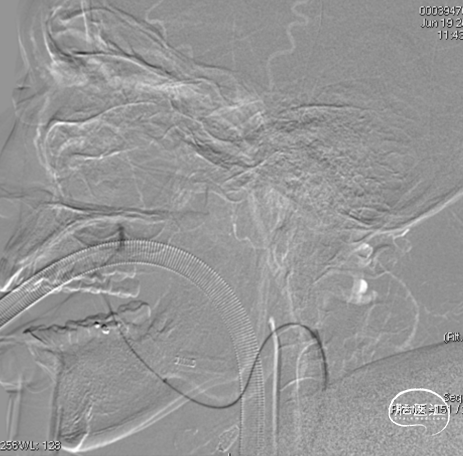

三枚弹簧圈对瘘口进行填塞,后通过Echelon微导管进行缓慢注胶,中途反复确认注胶形态。

术后铸胶形态及CT下铸胶位置,可见瘘口位于左侧舌下神经管区域。